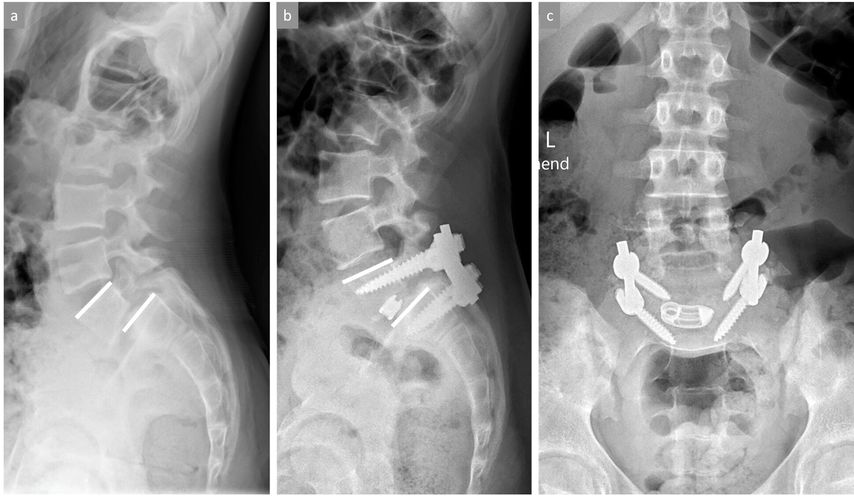

Wenn eine knöcherne Ausheilung der Spondylolyse bei symptomatischen Patienten sehr unwahrscheinlich ist (radiologisch sklerosierte, abgerundete Frakturränder des Pars-Defekts) und insbesondere bei gleichzeitigem Vorliegen einer leichtgradigen Spondylolisthese sind die Ergebnisse konservativer Massnahmen deutlich seltener nachhaltig erfolgreich und ein früheres operatives Vorgehen sollte zumindest angesprochen werden. Bei objektivierbarer Progression der Spondylolisthese und/oder neurologischen Symptomen ist die Indikation für eine operative Stabilisierung grundsätzlich gegeben. Bei fehlenden knöchern-dysplastischen Veränderungen und noch intakter Bandscheibe zwischen den betroffenen Wirbeln (i.d.R. L5/S1) kann ein sogenannter «direct pars repair» durchgeführt werden. Hierbei wird nach Resektion einer allfälligen Pseudarthrose der Defekt mit einer Schraube durch die Pars interarticularis direkt verschraubt oder alternativ ein Konstrukt aus Pedikelschraube und Laminahaken frakturüberbrückend bilateral eingebracht (Abb. 4). Wenn die Betroffenen nicht für einen «direct pars repair» qualifizieren, wird eine (instrumentierte) posterolaterale Fusion der betroffenen Segmente durchgeführt.

Abb. 4: Bild (a) zeigt ein stehendes seitliches Röntgenbild der LWS mit objektivierbarer isthmischer Spondylolyse (Pfeil) im Bereich der Pars interarticularis von LWK5 mit belgeitender leichtgradiger Spondylolisthese LWK5/SWK1. Bilder (b) und (c) zeigen die Situation nach erfolgter Operation mittels «direct pars repair», bei welcher der Pars-Defekt auf beiden Seiten durch ein Pedikelschrauben-Laminahaken-Konstrukt nach Resektion der Pseudarthrosezone überbrückt wird. Der weisse Pfeil im kleinen Bildausschnitt von Bild (b) zeigt eine vollständige knöcherne Ausheilung des ehemaligen Pars-Defekts

Eine höhergradige Spondylolisthese (≥Gleitgrad III) ist selbst bei fehlenden Beschwerden in aller Regel mit einer relevanten Störung des sagittalen Profils verbunden und sollte aufgrund der durchgehend schlechten Prognosen konservativer Therapieansätze operativ versorgt werden. Primäres Ziel dabei ist die Wiederherstellung der segmentalen Lordose und nicht die vollständige Reposition des Wirbelgleitens (Abb. 5). Das Erreichen einer zirkumferenziellen antero-postero-lateralen («360°») Fusion ist mit besseren Langzeitresultaten verbunden als alleinige anteriore oder posteriore Stabilisierungen.17

Abb. 5: Bild (a) zeigt eine hochgradige Spondylolisthese LWK5/SWK1 mit resultierender Kyphosierung in diesem Bewegungssegment. Bilder (b) und (c) zeigen die Situation nach erfolgter Operation mit partieller Reposition des Wirbelgleitens und Wiederherstellung der segmentalen Lordose mittels dorsaler Instrumentierung und ventralen Cages für eine zirkumferenzielle knöcherne Fusion